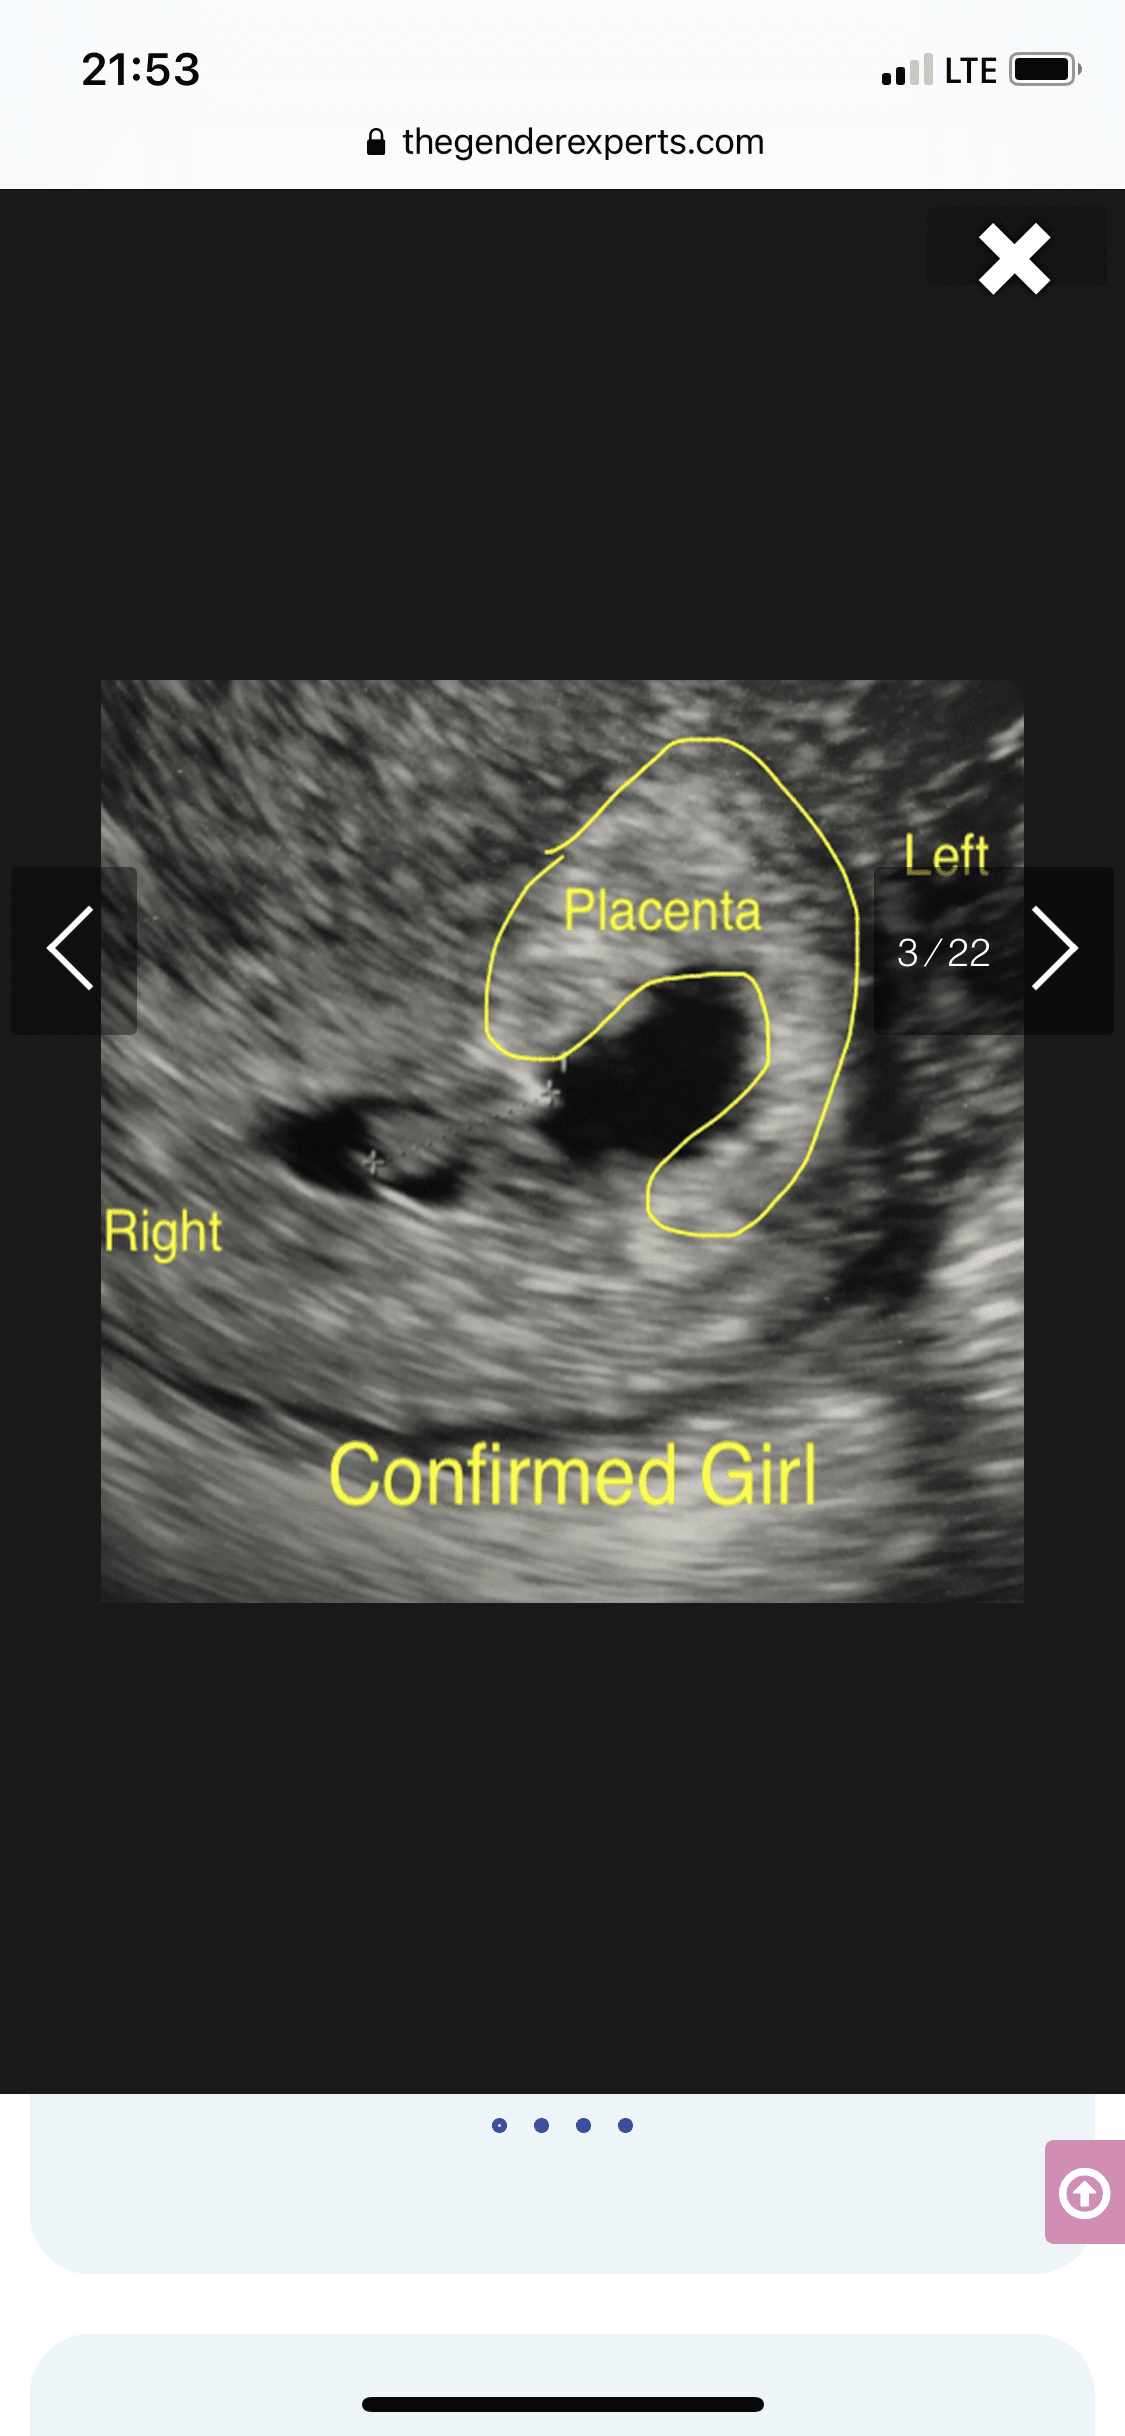

Tak dokładnie chodzi o położenie kosmowki z której potem wytworzy się łożysko. Metoda się sprawdza tak jak mówisz 50/50Aaa pytałam wtedy o położenie kosmowki.